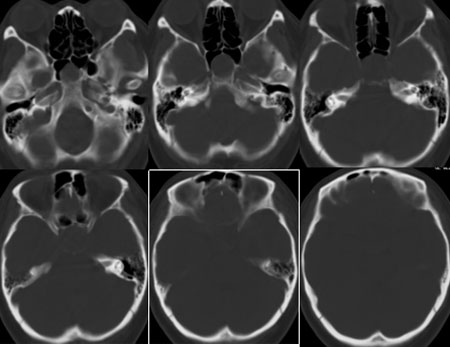

鞍区垂体窝内见一巨大类椭圆性软组织块影,前后床突受压移位、变薄,鞍底凹陷,应当能明确诊断垂体瘤。不过最好能做个mri看看视神经受累情况

蝶鞍内圆形密度不均匀,包膜完整肿块影,前床突与鞍底变薄.

意见:垂体大腺瘤.

本病例单凭ct检查是很难定位准确的,是鞍上病变侵犯鞍内、还是鞍内病变向鞍上生长?

1、如果鞍内肿瘤突破鞍隔,向鞍上生长,考虑垂体腺瘤,其典型表现是肿瘤呈"8"字征。

2、如果是鞍上肿瘤侵犯鞍内,要考虑鞍区脑膜瘤、生殖细胞瘤、实性颅咽管瘤(多为囊性、少数也可实性)、转移瘤、垂体柄胶质细胞瘤。